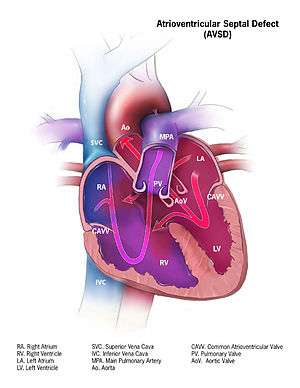

Illustration of a atrioventricular septal defect | |

Atrioventricular septal defect (AVSD) or atrioventricular canal defect (AVCD), previously known as "common atrioventricular canal" (CAVC) or "endocardial cushion defect", is characterized by a deficiency of the atrioventricular septum of the heart. It is caused by an abnormal or inadequate fusion of the superior and inferior endocardial cushions with the mid portion of the atrial septum and the muscular portion of the ventricular septum.

- In the complete AVSD (CAVSD), there is a large ventricular component beneath either or both the superior or inferior bridging leaflets of the AV valve. The defect involves the whole area of the junction of the upper and lower chambers of the heart, i.e. where the atria join the ventricles. There is a large hole between the lower portion of the atria and the upper or `inlet' portion of the ventricles and this is associated with a significant abnormality of the valves separating the atria from the ventricles. The valves in effect become a common atrio-ventricular valve, and the severity of the defect depends largely on the supporting attachments of the valve to the ventricles and whether the valve allows dominant flow from the right atrium to right ventricle and from left atrium to left ventricle ("unbalanced" flow). The overall problems are similar to those of VSD but are more complicated. There is an increased flow of blood to the lungs through both the ventricular and atrial components of the defect. In addition, the abnormal atrio-ventricular valve invariably leaks, so that when the ventricles contract, blood flows not only forwards to the body and the lungs, but also backwards into the atria. The back-pressure effect on the atria causes congestion of blood in the left atrium in particular, and this in turn causes congestion in the veins draining the lungs. The effect on the baby is to worsen the heart failure that is associated with an isolated VSD and to hasten the onset of pulmonary hypertension. It should be mentioned that CAVSD is found in approximately one-third of babies who have Down syndrome, but it also occurs as an isolated abnormality.